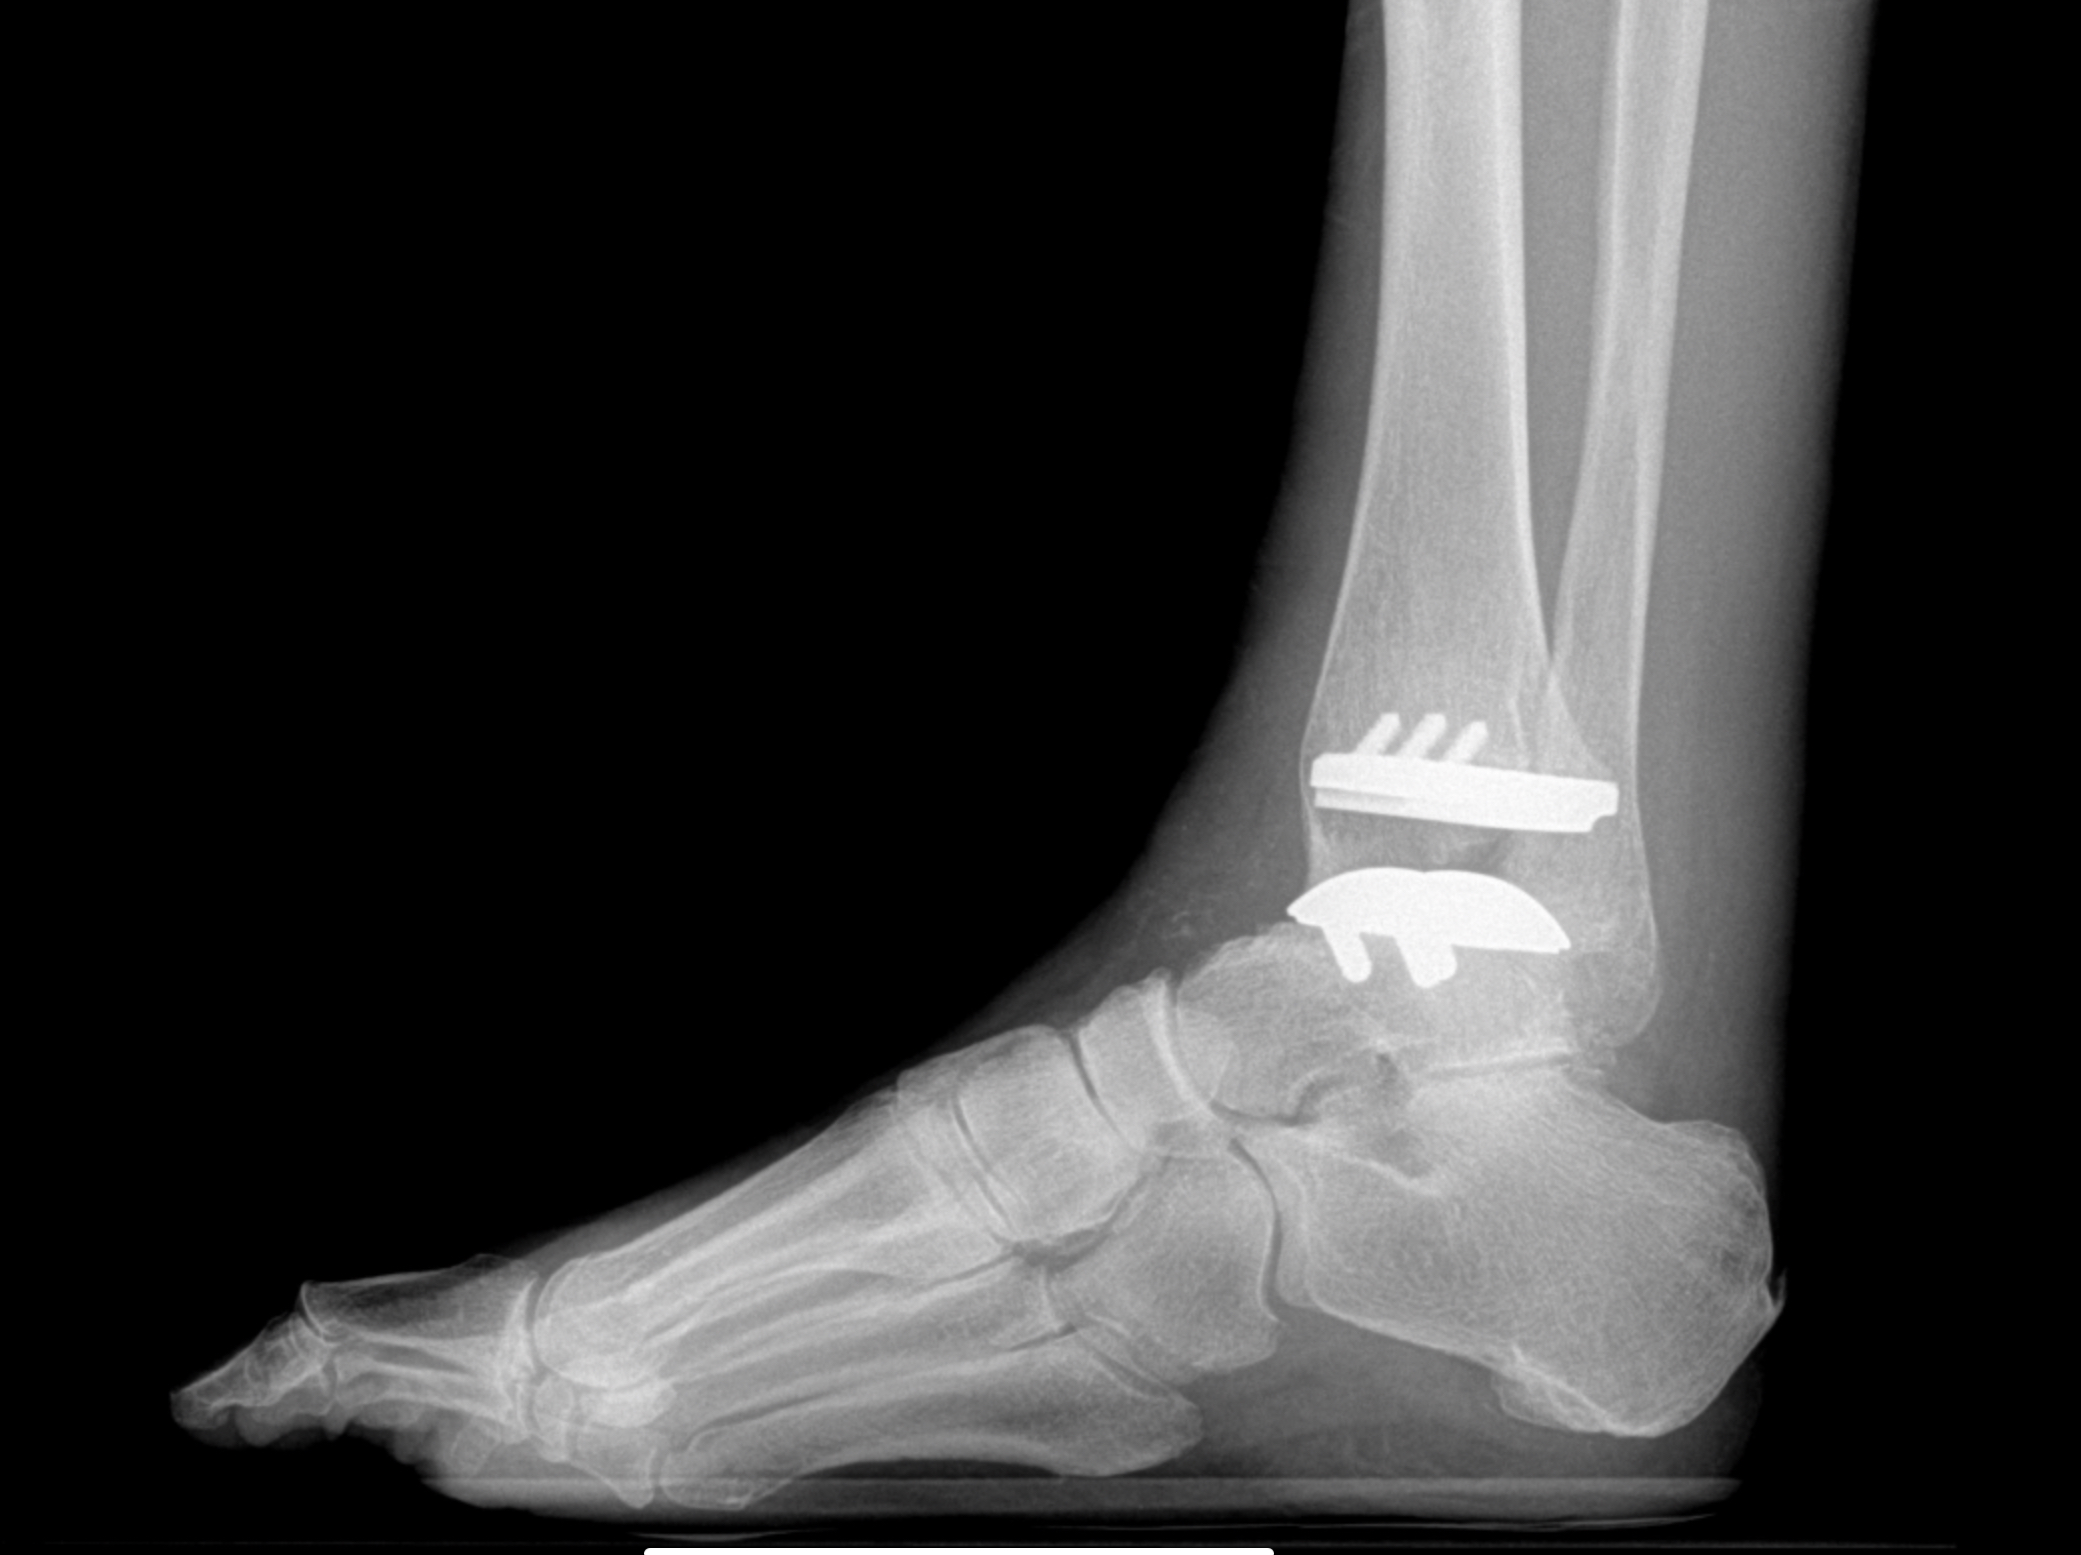

Foot & Ankle Replacement